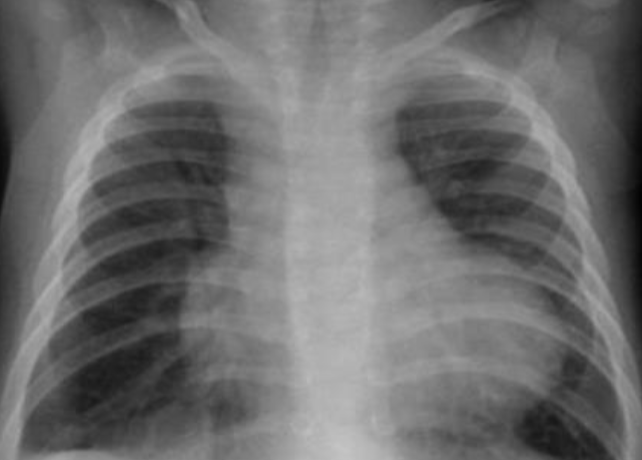

- AP chest film which shows complete opacification of the whole right lung - (1 .with shifted mediastinum and trachea to the left side

- .This indicates pleural effusion (PE) - (2

- After inserting chest tube, pus was coming out. This means that the PE is - (3 .an Empyema

- .The cause of this empyema is most likely a Bacterial Pneumonia - (4

- The age of the patient is 10 years which means that the most likely - (5 .organism is Streptococcus Pneumonae